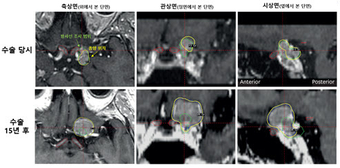

55세 여성 환자의 시신경 인접 수막종 수술 당시(상단)와 15년 후(하단) MRI 영상. 수술 당시 시신경 보호를 위해 종양 일부에 방사선을 쏘지 않았으나(커버리지율 74.4%), 15년 뒤 과거 방사선을 피했던 부위에서 종양이 다시 자라났다(하단). 재발 확인 후 방사선을 5번에 나눠 쏘는 '다분획(저분할) 감마나이프 수술'을 시행해 16개월 후 시력 저하 없이 종양을 현저히 축소시켰다.